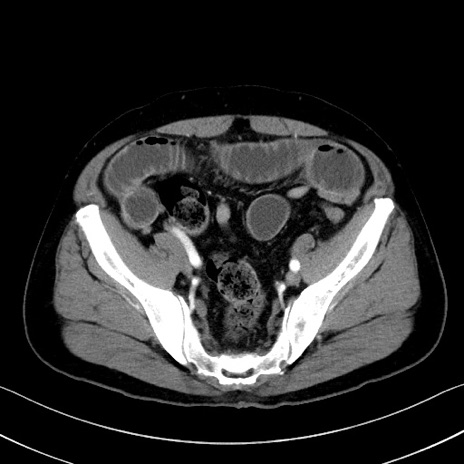

症例35(横断像)

冠状断像

【症例】70歳代 男性

【主訴】腹部膨満、嘔吐

【現病歴】昨日より腹部膨満感出現。本日増悪し、仙痛出現。嘔吐あり、受診。

【既往歴】糖尿病、胆摘後

【身体所見】BP 149/80mmHg、HR 74/min、BT 35.9℃、腹部:膨満、軟、圧痛なし。腸雑音減弱あり。上腹部正中切開瘢痕あり。

【データ】WBC 13500、CRP 1.72